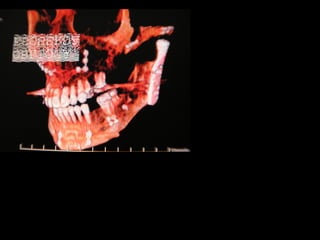

Deflección craneal 26º

Longitud craneal anterior 59 mm.

Altura posterior facial 59 mm.

Posición de rama mandibular 78º

Localización de Porión 38 mm.

Arco mandibular 30º

Longitud de cuerpo mandibular 81 mm.